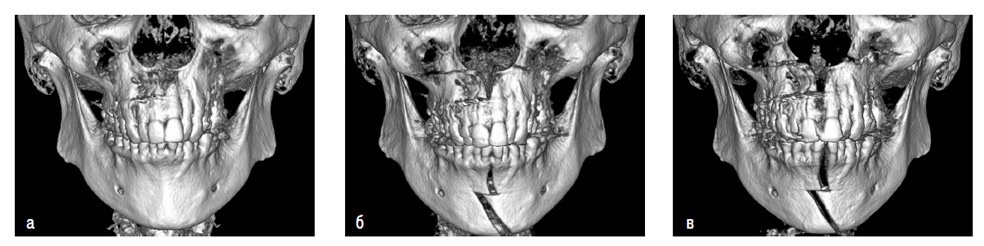

Рис. 10. Пациент Б. 47 лет. Ds: СЗЧЛА, дистальный прикус, сужение верхней и нижней челюстей. Исследования конусно-лучевой компьютерной томограммы, 3D-реконструкция: а – до операции, б – контроль в день операции, в – контроль при получении достаточного расширения (1 месяц), г – контроль созревания костного регенерата перед снятием аппарата (4 месяца), д – контроль через 10 месяцев с момента операции